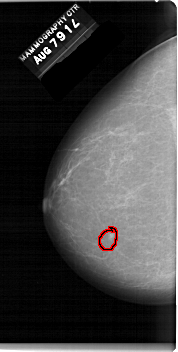

A_1541_1.LEFT_MLO

LEFT_MLO LINES 6421 PIXELS_PER_LINE 3526 BITS_PER_PIXEL 12 RESOLUTION 43.5 OVERLAY

FILE: A_1541_1.LEFT_MLO.OVERLAY

TOTAL_ABNORMALITIES 1

ABNORMALITY 1

LESION_TYPE MASS SHAPE OVAL MARGINS CIRCUMSCRIBED

ASSESSMENT 4

SUBTLETY 4

PATHOLOGY BENIGN

TOTAL_OUTLINES 1

BOUNDARY